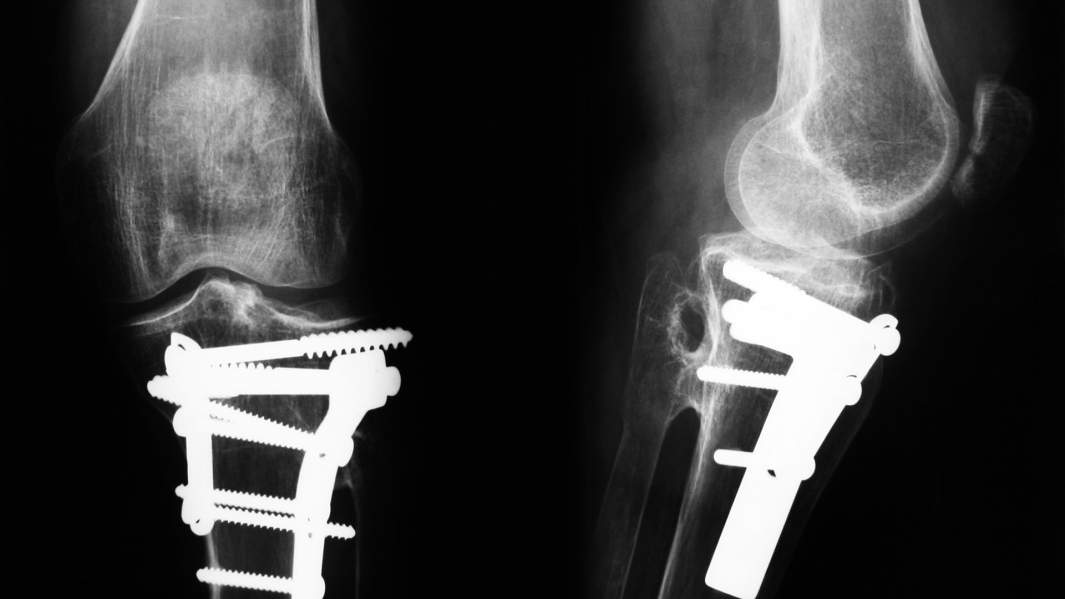

Идея ученого состояла в том, чтобы вывести на российский рынок импланты из углеродных композиционных материалов, в частности карбона, рассказал «Известиям» представитель пресс-службы холдинга «Швабе».

На тот момент подобная продукция в России не производилась — импортировалась из США, Израиля, Германии и других стран. По словам представителя холдинга, речь идет об имплантах костей черепа, тел позвонков, пластин и винтов для шеи, а также об эндопротезах тазобедренного сустава.

Импланты из углеродных композиционных материалов также широко применяются в стоматологии, пояснил «Известиям» замдиректора Центра НТИ «Цифровое материаловедение: новые материалы и вещества» МГТУ им. Н.Э. Баумана Павел Елизаров.

— Они обладают высокой биологической совместимостью с телом человека, — уточнил ученый. — Их свойства можно максимально приблизить к естественной костной ткани. Они дольше служат и не позволяют деградировать здоровой костной ткани.

По версии «Швабе», Валерий Медик не получил даже разрешения Росздравнадзора на клинические исследования — из-за несоответствий его разработки техническим требованиям и санитарным нормам. Прототип изделия был изготовлен из карбона, который имеет свойство расслаиваться в организме, уточнили в холдинге. Иностранные компании для предупреждения подобного свойства обрабатывают импланты специальным покрытием, но для его производства в России технологий пока нет, добавили там.

— Валерий Медик использовал материал, отличающийся от нашего и одобренного всеми инстанциями. Проблема того материала, который он взял, — игольчатая структура. Иголки отламываются, и образуется маленькая заноза внутри организма, вокруг которой может возникать опухоль, — рассказал Олег Барзинский.